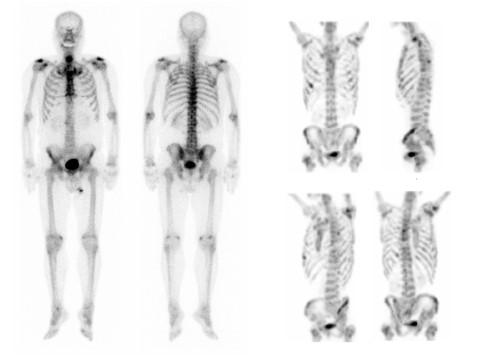

【骨シンチ検査】

骨の病気を早い段階で見つけるために必要な検査です。全身の骨の状態や、断層撮影にて微細な異常を診断します。